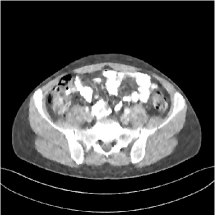

III.C.2. Simulation Framework, Reconstruction Results, and Comparisons

The synthesized low-dose clinical measurements are simulated from regular-dose images at a resolution of mm with a fan-beam CT geometry corresponding to a monoenergetic source at incident photon intensity . The sinograms are of size . The width of each detector column is mm, the source to detector distance is mm, and the source to rotation center distance is mm. We reconstruct images of size with the pixel size being mm mm.

We conducted experiments on one test slice used for parameter tuning (L067-slice 120) and four independent test slices (L109-slice 90, L192-slice90, L333-slice140, L506-slice 100) of the Mayo Clinic data. For PWLS-EP, we ran iterations using relaxed OS-LALM and set regularization parameter . We used the same as the phantom experiments for Algorithm 2. The process of selecting a general set of reconstruction parameters () for the Mayo Clinic test slices is identical to that for the XCAT phantom in Section III.B.2. The selected regularization parameter and the parameters that control the sparsity of the coefficient maps are for ST, , , , , for MARS2, , , , , , , for MARS3, , , , , , , , , , , for MARS5, and , , , , , , , , , , , , , , for MARS7, respectively.

Figs. 8, 9, 10, and 11 show the reconstructions of the four independent slices using the FBP, PWLS-EP, PWLS-ST, PWLS-MARS2, PWLS-MARS3, PWLS-MARS5, and PWLS-MARS7 schemes, respectively. Additional Mayo Clinic experimental results of the parameter tuning case (Fig. 15) are shown in the supplementary document. Table 1 lists the RMSE and SSIM values of reconstructions of the four independent test slices, with the best values bolded. Generally, the five and seven layer models provided the best RMSE and SSIM values. They outperform the single-layer model by HU in RMSE on average. However, the MARS5 and MARS7 models perform similarly. In order to strengthen the benefits of the multi-layer model, Table 2 lists the RMSE of the reconstructions in four different ROIs (shown in the reference of Fig. 11) with seven methods for slice 100 of patient L506. By observing the reconstructed images, we see that although the ST model achieves a cleaner reconstruction result than FBP and PWLS-EP, it still sacrifices some sharpness of the central region and suffers from loss of details. The deeper models have a somewhat more positive effect in terms of maintaining subtle features, which is clearly more essential to clinical diagnosis. Furthermore, as we will discuss later, after considerable parameter tuning, we found that the information contained in residual maps is gradually decreased with the number of layers, eventually vanishing at some layer, which suggests that very deep unsupervised models might not offer significantly better image quality.